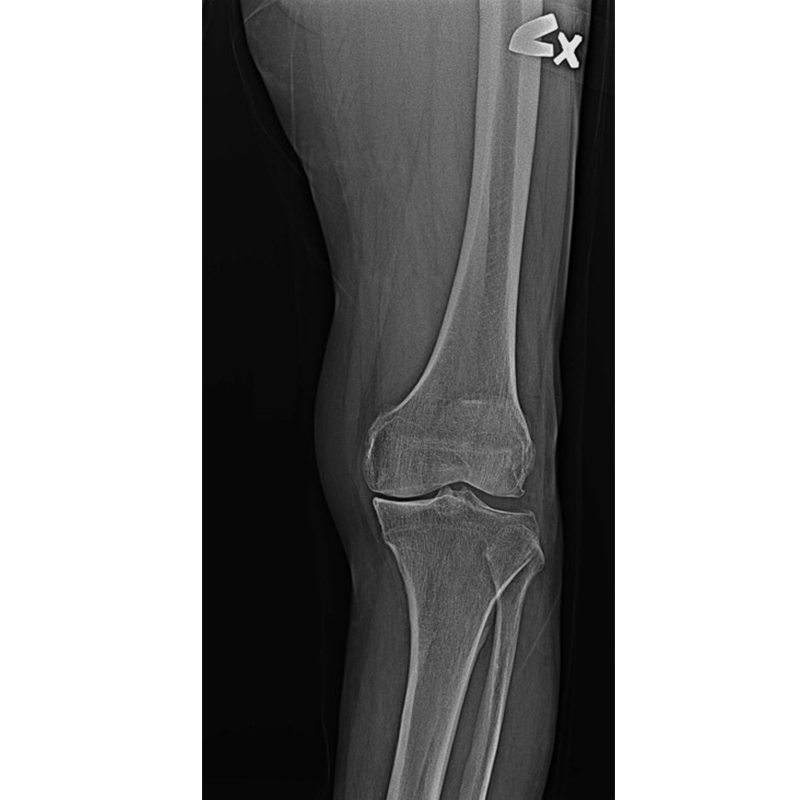

傳統部分膝置換 首頁 案例分享 膝關節手術 傳統部分膝置換 殷女士 65歲 術前 術後 張女士 71歲 術前 術後 蔡女士 74歲 術前 術後 張女士71歲 術前 術後 翁女士70歲 術前 術後 劉女士 80歲 術前 術後